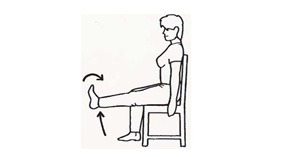

زانو را خم کنید و پا را از روی زمین بلند کنید. 5 ثانیه در این حالت بمانید. این حرکت را 10 بار تکرار کنید.

زانو را تا جایی که میتوانید خم کنید یا این که در روشی دیگر، پای سالم را روی پای عمل شده بیاندازید و پای عمل شده را رو به عقب و به سمت خودتان بکشید. این حرکت را 10 بار تکرار کنید.